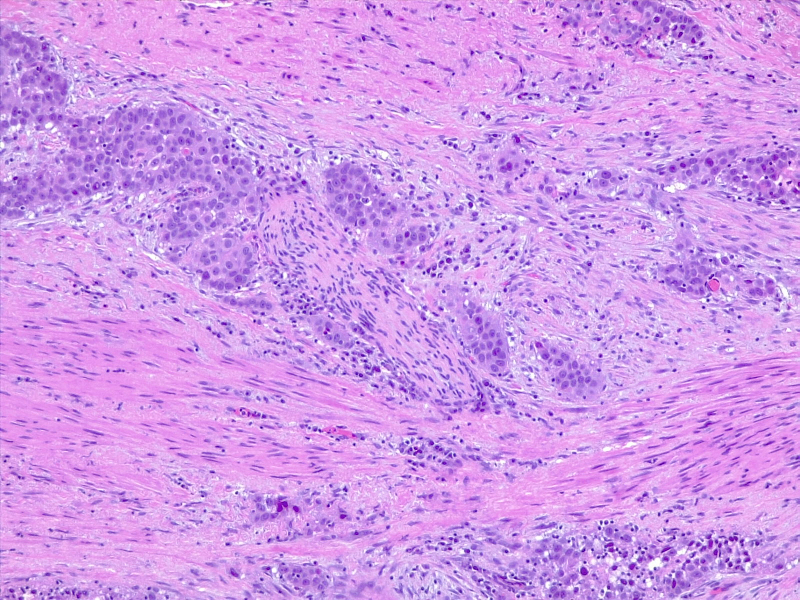

Poorly differentiated urothelial carcinoma, with metaplastic squamous appearance

圖3: 分化差的尿路上皮癌,具有化生性鱗狀外觀。10x,H/E。醫(yī)學(xué)博士 Fabiola Farci 供稿